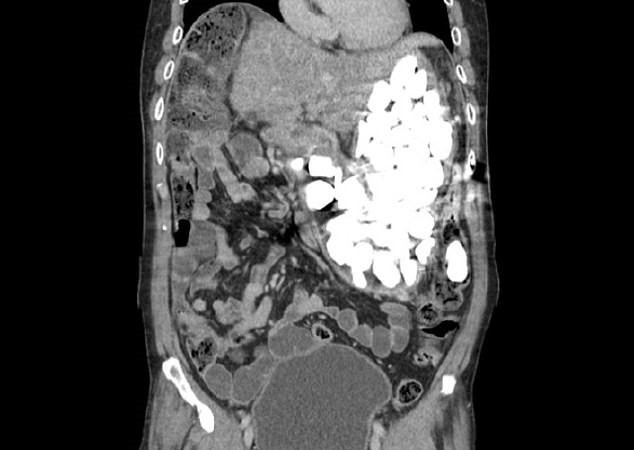

20/02/2019 15:52Đau bụng dữ dội vì 2 kg đá, đồng xu mắc kẹt trong dạ dày

Theo Daily Mail, bệnh nhân 54 tuổi, giấu tên, đến từ Goyang, Hàn Quốc. Sau khi bị đau bụng dữ dội, bệnh nhân tới bệnh viện Ilsan Paik thuộc Đại học Inje để khám. Theo quan sát ban đầu, các bác sĩ nhận thấy bệnh nhân bị đầy hơi và cảm thấy "có gì đó giống như những viên đá nhỏ" khi họ chạm vào bụng bệnh nhân.

Hình ảnh chụp X-quang cho thấy có một nhóm dị vật lạ, số lượng lớn chiếm lấy toàn bộ dạ dày của bệnh nhân.

Các bác sĩ ban đầu nội soi dạ dày để loại bỏ các dị vật bằng một ống mỏng đưa vào dạ dày qua miệng. Tuy nhiên, nó đã thất bại vì số lượng các dị vật trong dạ dày quá nhiều. Họ không đếm được có bao nhiêu dị vật mà người đàn ông đã nuốt.

Ngày hôm sau, nhóm bác sĩ buộc phải phẫu thuật để loại bỏ chúng. Họ bất ngờ khi nhìn thấy đá cuội, tiền xu và nắp chai trong dạ dày bệnh nhân. Khi được hỏi, bệnh nhân thú nhận ông thường nuốt đồng xu và đá cuội bất cứ khi nào cảm thấy lo lắng, mặc dù đã uống thuốc để trấn tĩnh. Không rõ các dị vật này đã ở bên trong cơ thể bệnh nhân bao lâu, ông chỉ nói đó là thói quen trong quá khứ. Bệnh nhân sau đó đã được về nhà sau 9 ngày điều trị tại bệnh viện.